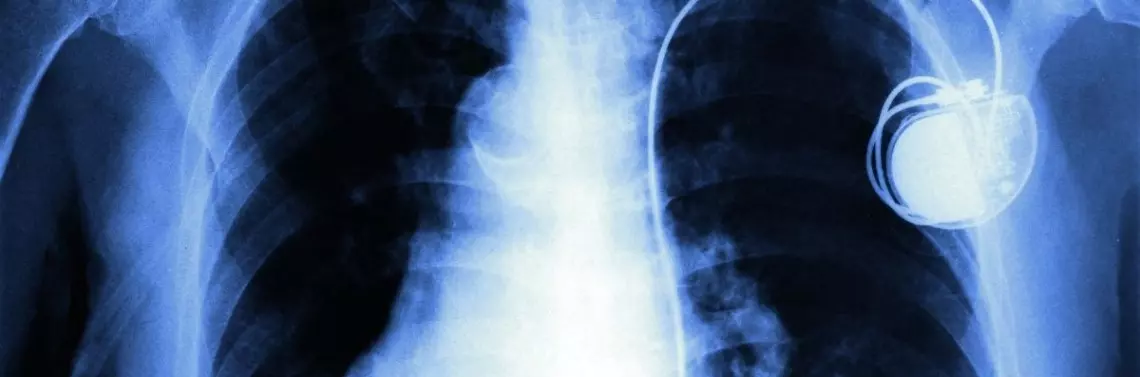

Układ stymulujący jest złożony z generatora impulsów oraz z jednej lub więcej elektrod. Elektrody umiejscowione są w jamach serca (prawy przedsionek, prawa komora) lub układzie żylnym serca (żyły uchodzące do zatoki wieńcowej). Impuls elektryczny dostarczany przez stymulator rozprzestrzenia się za pomocą elektrod i powoduje skurcz przedsionków i komór, dzięki czemu serce może pracować z odpowiednią częstotliwością. Stymulatory implantuje się pacjentom z objawową bradykardią, tzn. z omdleniami, zawrotami głowy, mroczkami przed oczami w przebiegu zaburzeń rytmu i przewodzenia lub pacjentom z niewydolnością serca i blokiem lewej odnogi pęczka Hisa (tzw. stymulacja resynchronizująca). Najczęstsze schorzenia, które wymagają stymulacji serca, to choroba węzła zatokowego, napadowe lub utrwalone bloki przedsionkowo-komorowe. Wskazania do tego typu zabiegów są ustalone i zebrane w wytycznych Europejskiego Towarzystwa Kardiologicznego (European Society of Cardiology – ESC) dotyczących stymulacji serca. Ostatnia wersja tego dokumentu została opublikowana w sierpniu 2013 r. Zaktualizowano w nim sposoby postępowania w zakresie tej metody leczenia schorzeń serca. Pierwszy zabieg implantacji rozrusznika wykonano w Szwecji w 1958 r., w Polsce – w 1963 r. W 2012 r. w Polsce wszczepiono ok. 30 000 stymulatorów serca.